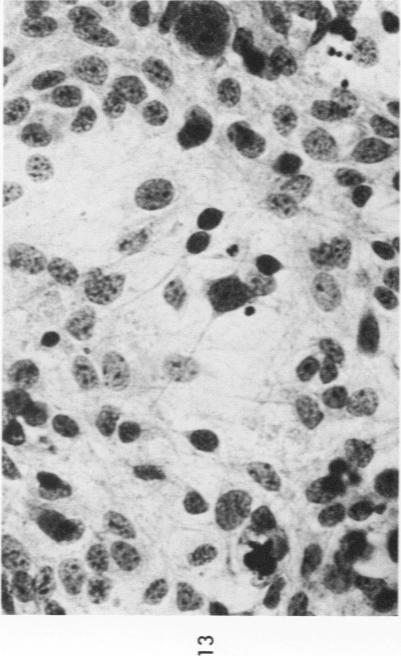

The various stages of divergent neuroepithelial differentiation were studied in the solid transplants of a transplantable mouse testicular teratoma (OTT-6050) maintained in both ascitic and solid forms. They included: a) areas of undifferentiated medullary epithelium corresponding to the rare human medulloepithelioma; b) areas of neuroblastic differentiation corresponding to neuroblastoma, with more mature neuronal differentiation corresponding to ganglioneuroma or, when mixed with glial elements, to ganglioglioma; and c) more mature neuroglial areas resembling astrocytoma, oligodendroglioma or ependymoma, as well as more primitive areas corresponding to ependymoblastoma. In tissue culture using collagen-coated coverslips, astrocytic differentiation was found in the outgrowth zone after 15 days, confirmed by immunofluorescence with antibodies to an astroglia-specific protein. In organ culture systems, glial components, including ependymal structures, were preserved in tumor explants, and astrocytic differentiation, as expressed by glial fiber formation, was increased after 4 to 6 weeks in vitro. No neuronal differentiation was demonstrable, however. The neuroepithelial component of this experimental teratoma may provide a model for the study of neoplastic neuroepithelial differentiation.

在以腹水和实体形式维持的可移植小鼠睾丸畸胎瘤(OTT - 6050)的实体移植中,研究了神经上皮分化的各个阶段。这些阶段包括:a)与罕见的人类髓上皮瘤相对应的未分化髓上皮区域;b)与神经母细胞瘤相对应的成神经细胞分化区域,与神经节神经瘤相对应的更成熟的神经元分化区域,或者当与神经胶质成分混合时,与神经节胶质瘤相对应的区域;c)更成熟的类似星形细胞瘤、少突胶质细胞瘤或室管膜瘤的神经胶质区域,以及与室管膜母细胞瘤相对应的更原始区域。在使用胶原包被盖玻片的组织培养中,15天后在生长区发现了星形细胞分化,用抗星形胶质细胞特异性蛋白的抗体进行免疫荧光证实。在器官培养系统中,肿瘤外植体中保留了包括室管膜结构在内的神经胶质成分,体外培养4至6周后,以胶质纤维形成为特征的星形细胞分化增加。然而,未发现神经元分化。这种实验性畸胎瘤的神经上皮成分可能为肿瘤性神经上皮分化的研究提供一个模型。